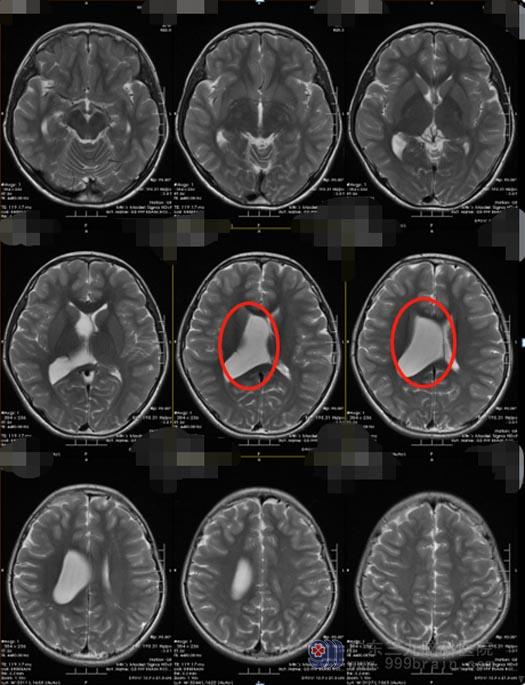

随着时间的推移,成成诉说头晕头痛的次数越来越多,特别是近2个月,由开始的每周一两次到后来的一天好几次,时常还伴有呕吐,妈妈这才警觉起来,再次带儿子到当地医院就诊,头颅MR检查提示:右侧侧脑室内囊状灶,考虑蛛网膜囊肿。

妈妈一下子慌了神,她觉得非常愧疚,自己错怪儿子了。她决定这次一定要带着孩子去更加专业的医院仔细看看。在广东三九脑科医院进行了相关的专科检查后,医院副院长、神经外五科主任鲁明告诉成成妈妈:小成脑室内囊状灶不是蛛网膜囊肿,而是较为罕见的神经上皮囊肿。

成成的手术指征明确,其囊肿充斥了整个右侧侧脑室,开颅手术易引起出血,创伤也较大,若没有完全切除,术后容易复发;选择内镜辅助下进行囊肿切除术,不但创伤小,并且效果也较好。在制定了严密的手术方案之后,成成顺利完成了“神经内镜辅助下右侧侧脑室病变切除术”,囊肿被完全切除。术后,成成恢复良好,头晕、头痛症状消失。